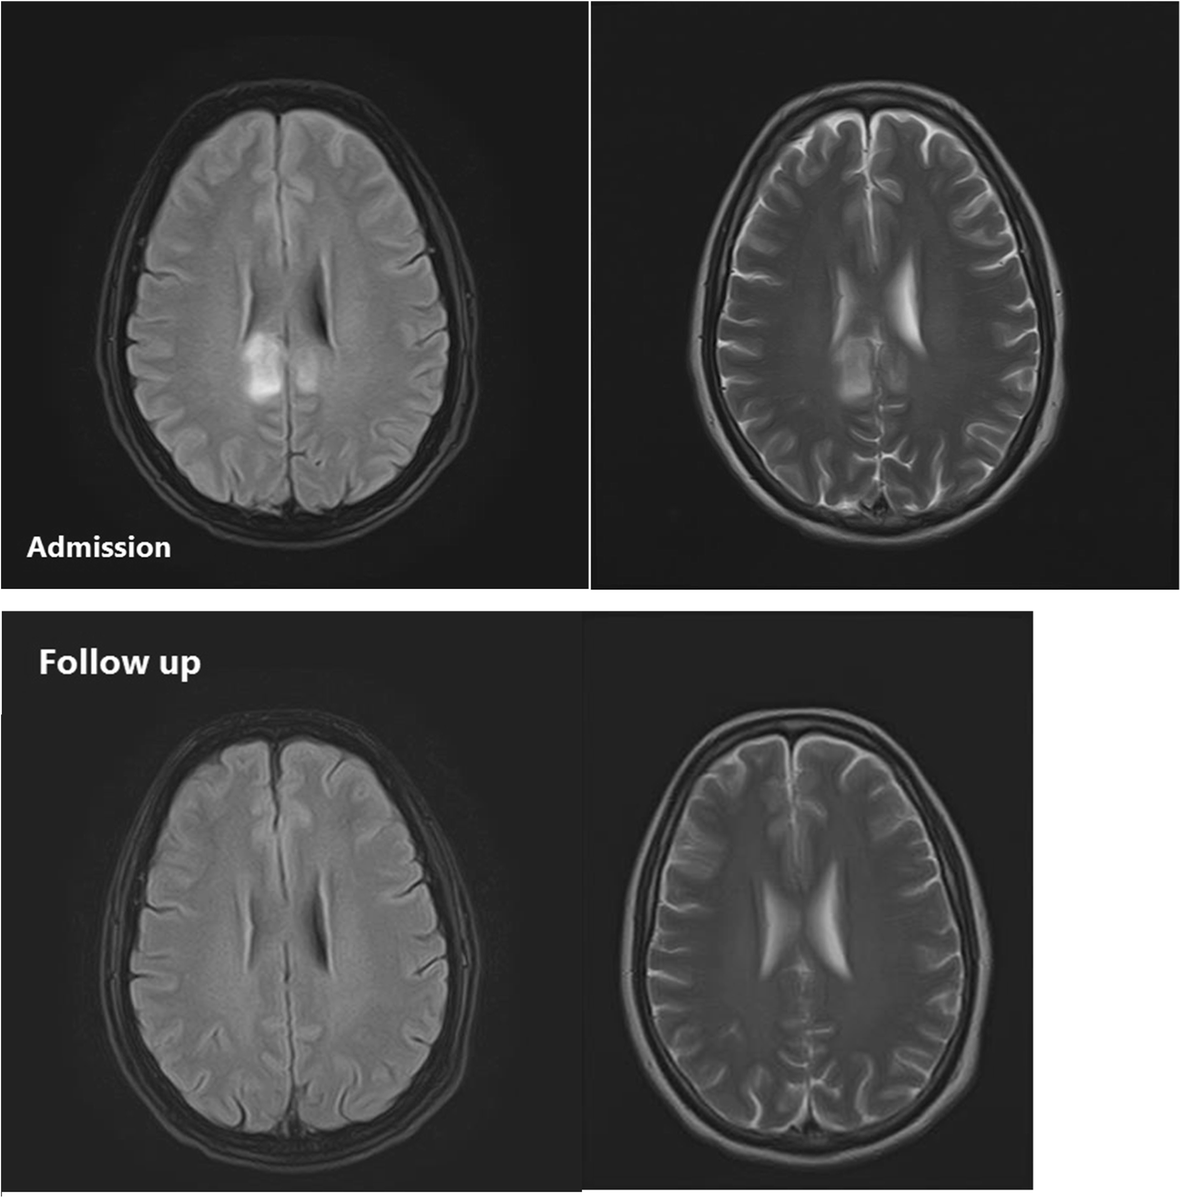

From www.ajnr.org

Pre and Posttreatment MR Imaging Findings in Lead Encephalopathy Lead Encephalopathy Radiology Encephalopathy is an uncommon but serious presentation of lead toxicity. Adult hypoglycemic encephalopathy or hypoglycemic brain injury is caused by an imbalance between supply and. Lead encephalopathy is almost always associated. Lead poisoning affects multiple organs: Lead poisoning is a common occupational health hazard in developing countries. The differential diagnosis of patients presenting with acute encephalopathy is broad. Recognizing the. Lead Encephalopathy Radiology.